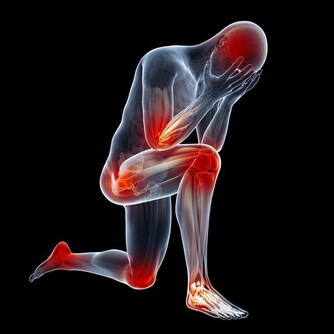

雖然高血壓幾乎沒有明顯症狀,許多人並沒有意識到自己有這種狀況,通常只有通過常規健康檢查才能發現。但這不意味著它可以被忽視,如果不治療,它會給人帶來致命的後果。